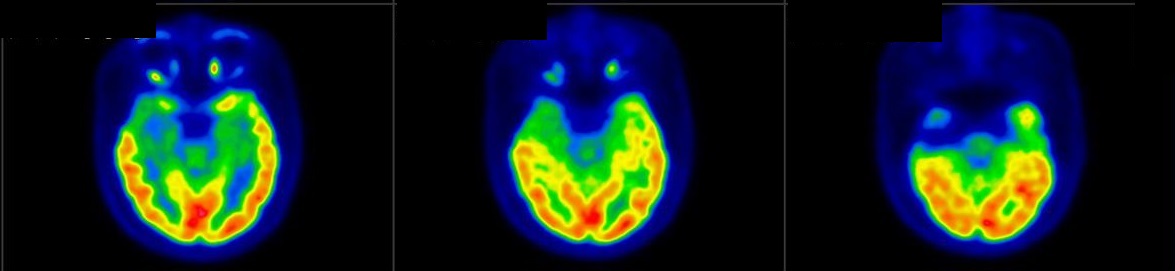

Neurological Diseases

- Dementia

PET/CT scans with special tracers can show 3-dimensional images of blood flow and biomolecules deposition in the brain for diagnosis and monitoring the therapy progress of various neurological diseases, such as Alzheimer's, Dementia, Parkinson's disease, Huntingdon's chorea and autism. In 2018, the National Institute on Aging-Alzheimer's Association (NIA-AA) had revised the definition of Alzheimer's Disease (AD) from a syndrome diagnosed by a set of clinical criteria to a biological construct using abnormal protein deposits to define AD as a unique neurodegenerative disease that can lead to dementia. Our hospital has almost 20 years of experience in producing specific tracer to detect abnormal protein deposition in the brain.